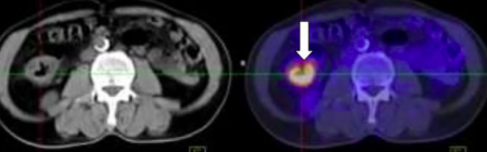

Hình ảnh khối u đại tràng phải, kích thước 3x4cm của bệnh nhân H.

Sau 6 chu kỳ hóa trị kết hợp Bevacizumab, các tổn thương u nguyên phát, di căn hạch ổ bụng, nốt di căn phổi đã không còn, chất chỉ điểm khối u CA 19-9 giảm. Tuy nhiên tổn thương di căn gan vẫn tồn tại và kích thước tổn thương gan đã thuyên giảm. Bệnh đáp ứng một phần với điều trị.